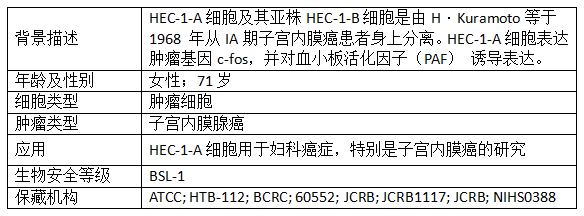

产品信息: